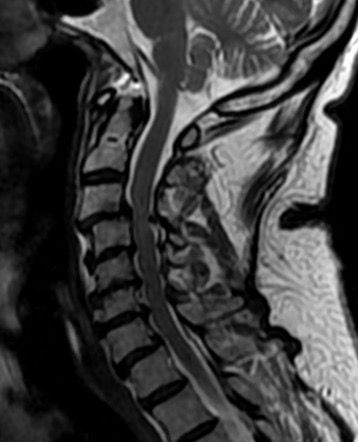

Discectomía cervical anterior y fusión

Cirugía malformación de Chiari